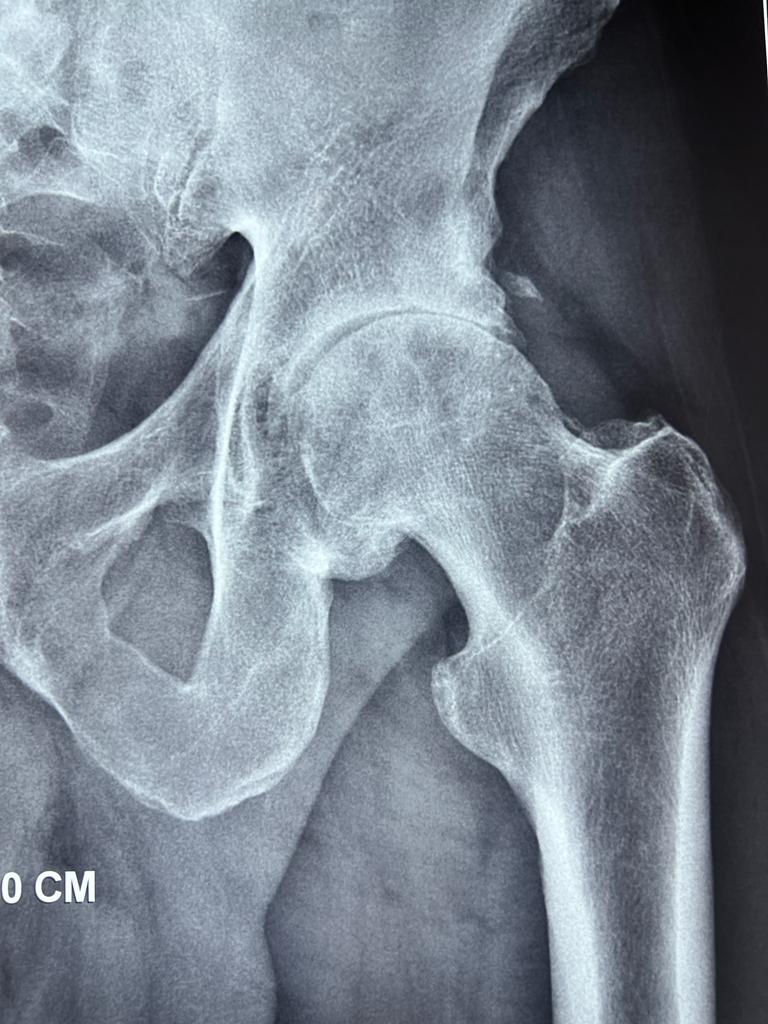

El Doctor Jorge Guadilla forma parte de la Unidad Especializada de Cadera de la UCA junto al Dr. Nicolás Fiz y la Dra. Ane Miren Bilbao.

En esta píldora audiovisual desgrana las causas, consecuencias y recomendaciones derivadas de la artrosis de cadera, una patología degenerativa.